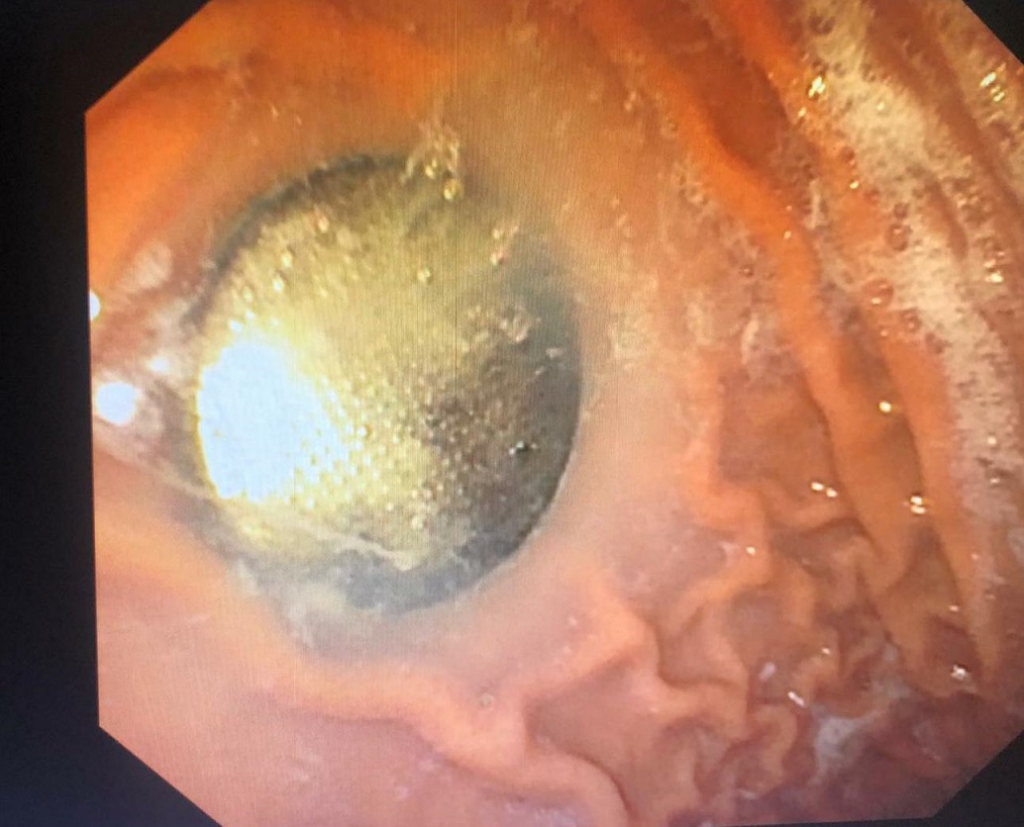

צילום: הקריה הרפואית רמב"ם.